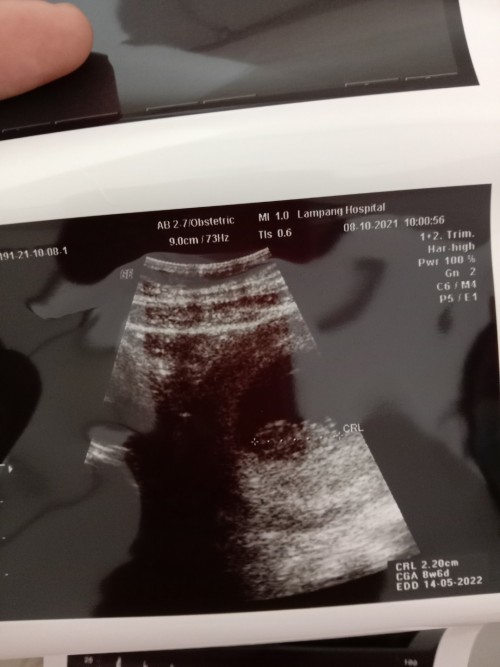

ซาวตอน10วีค5วัน ตอนนี้12วีคแล้วจ้า